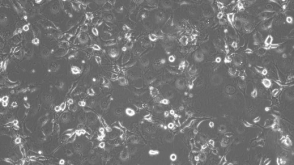

上皮细胞生物学,干细胞生物学,疾病建模,类器官,药物发现和毒理检测

点播Pulmonary Course Learn how to culture human airway epithelial cells (HAECs) at the air-liquid interface (ALI).